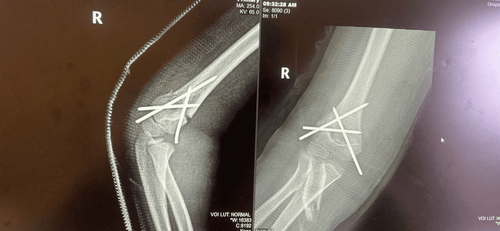

Kỹ thuật giúp bé trai 7 tuổi bị gãy tay hồi phục nhanh, không để lại sẹo

Nhờ áp dụng kỹ thuật nắn chỉnh, găm đinh kín tại Bệnh viện Đa Khoa Vinmec Hải Phòng, bé trai 7 tuổi bị ngã gãy tay, đã giảm đau nhanh, hồi phục tốt và xuất viện chỉ sau 1 ngày phẫu thuật.